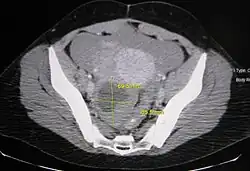

Ovarian cysts are usually diagnosed by pelvic ultrasound, CT scan, or MRI, and correlated with clinical presentation and endocrinologic tests as appropriate.[15] Ultrasound is the most important imaging modality, as abnormalities seen in a CT scan sometimes prove to be normal in ultrasound.[5][8] If a different modality is needed, then MRIs are more reliable than CT scans.[5]

Ovarian cysts are considered large when they are over 5 cm and giant when they are over 15 cm. In children, ovarian cysts reaching above the level of the umbilicus are considered giant.